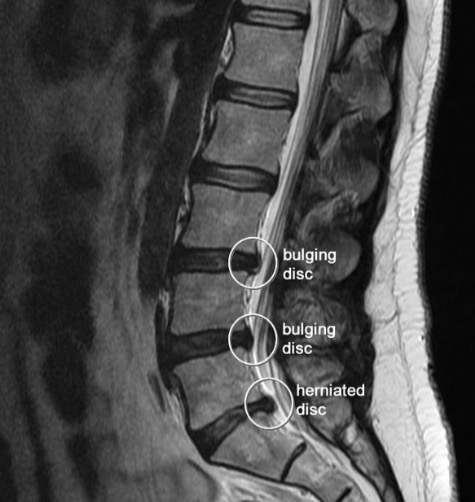

Sagittal MRI of herniated L5-S1 lumbar disc. #LowerBackPain | Bulging …

Magnetic Resonance Imaging or Mri Scan Report of Spinal Cord or Lumbar …

Pre-operative lumbar MRI showing a right paracentral disc herniation at …

MRI of a Lumbar-Disk Herniation – License, download or print for £9.92 …

Herniated Disc Mri L5 S1 – Lumbar Herniated Disc – A More in Depth Look …

Medical Endeavors w/ my Herniated and Degenerative Lumbar Disc: MRI …

Disc Herniation, Ct Myelogram Photograph by Living Art Enterprises …